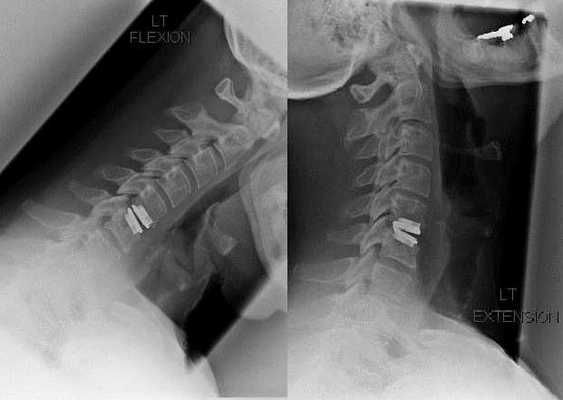

Хирургическое вмешательство

Показаниями к хирургическому вмешательству становятся неэффективность консервативного лечения, а также возникшие осложнения шейного остеохондроза, например, дискогенная миелопатия, синдром позвоночной артерии, корешковый синдром. Для декомпрессии спинного мозга, кровеносных сосудов, спинномозговых корешков проводятся следующие операции:

В процессе хирургического вмешательства могут иссекаться костные фрагменты, связки, удаляться полностью или частично межпозвонковые диски. При некрупном грыжевом выпячивании часто проводится лазерная вапоризация дискового ядра.

После иссечения позвоночных структур нередко требуется стабилизация позвоночно-двигательных сегментов методом спондилодеза или установкой костных, дермальных аутотрансплантатов.